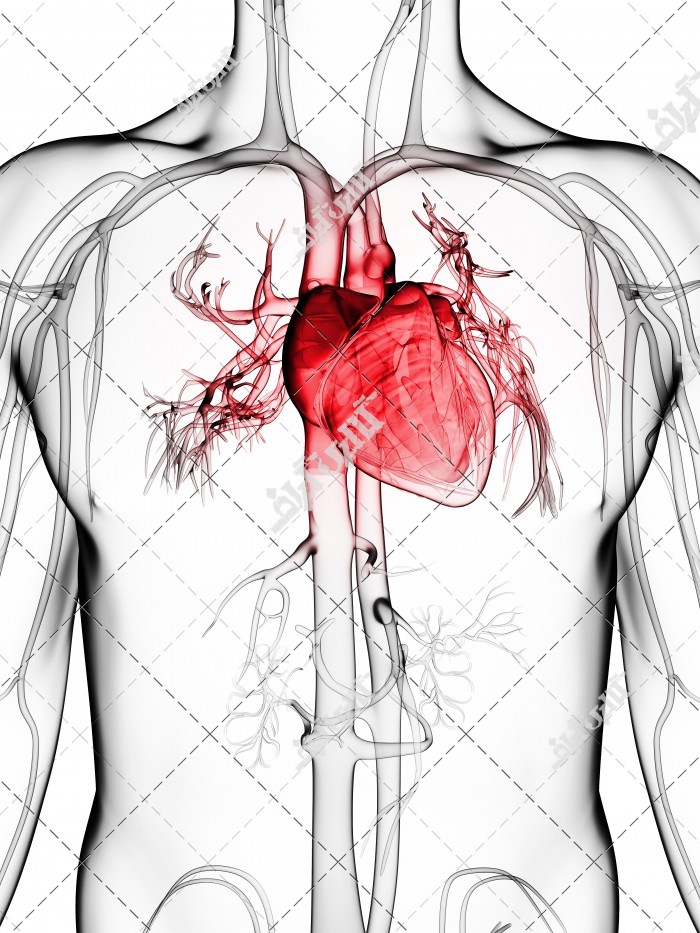

عکس اسکلت بدن انسان با کیفیت. عکس اسکلت عکس اسکلت برای پروفایل عکس اسکلت انسان عکس اسکلت خفن عکس اسکلت بدن انسان با کیفیت عکس اسکلت بدن انسان عکس اسکلت ترسناک عکس اسکلت فانتزی عکس اسکلت فانتزی دخترانه پرچم عکس اسکلت. عکس با کیفیت اسکلت داخلی انسان و درد و گرفتگی در ناحیه استخوان زانو ویژه استفاده در امور تبلیغاتی و تجاری طراحی کاتالوگ بروشور و تراکت با موضوع پزشکی فیزیوتراپی ارتوپد دکتر روماتیسم فیریوتراپ طب فیزیکی. عکس اسکلت بدن انسان زن و مرد آناتومی ساتین 16 سپتامبر 2017. اسکلت داربست بدن است تمام قسمت های بدن روی اسکلت قرارگرفته اند بدن انسان از ۲۰۶ قطعه استخوان تشکیل شده است این استخوان ها طوری با نظم کنار هم قرار گرفته اند که انسان را قادر می سازد حرکات دقیقی داشته باشد.

اسکلت جمجمه و گردن انسان ستون فقرات آناتومی اسکلت جمجمه و گردن انسان ستون فقرات آناتومی تصویر با کیفیت را از لینک زیر می توانید دانلود کنید. ۱ مطلب با کلمه ی کلیدی عکس اسکلت بدن انسان با کیفیت ثبت شده است گالری نسیم جدید ترین و با کیفیت ترین عکس های مناسبتی. عکس با کیفیت آناتومی اسکلت بدن انسان و درد و دیسک در قسمت مهره های ستون فقرات کمر ویژه استفاده در امور تبلیغاتی و تجاری طراحی کاتالوگ بروشور و تراکت با موضوع بیمارستان ها و کلینیک ها و درمانگاه ها و مطب ها پزشکان و.